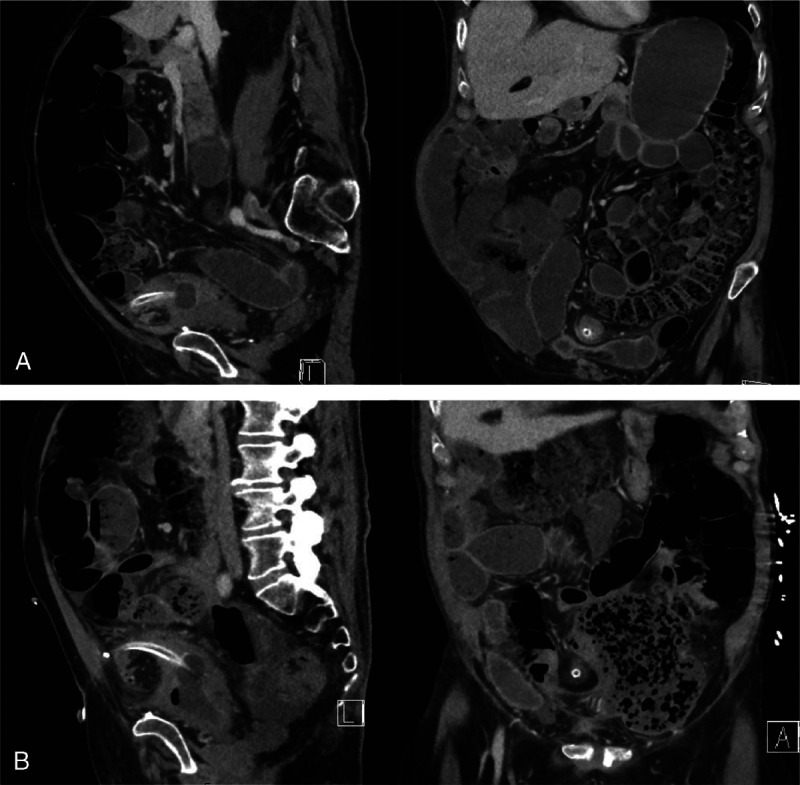

Although suprapubic cystotomy for catheter insertion is commonly performed, complications can be associated with serious morbidity. This case describes delayed recognition of a transperitoneal suprapubic catheter (SPC) traversing the small bowel mesentery and causing a closed loop obstruction of the caecum 7 years after SPC insertion. There are very few cases in the literature of SPC causing mesenteric perforation and to the best of our knowledge, this is the first reported case causing subsequent obstruction of the caecum and the longest delay of 7 years between SPC insertion and manifestation of bowel obstruction.